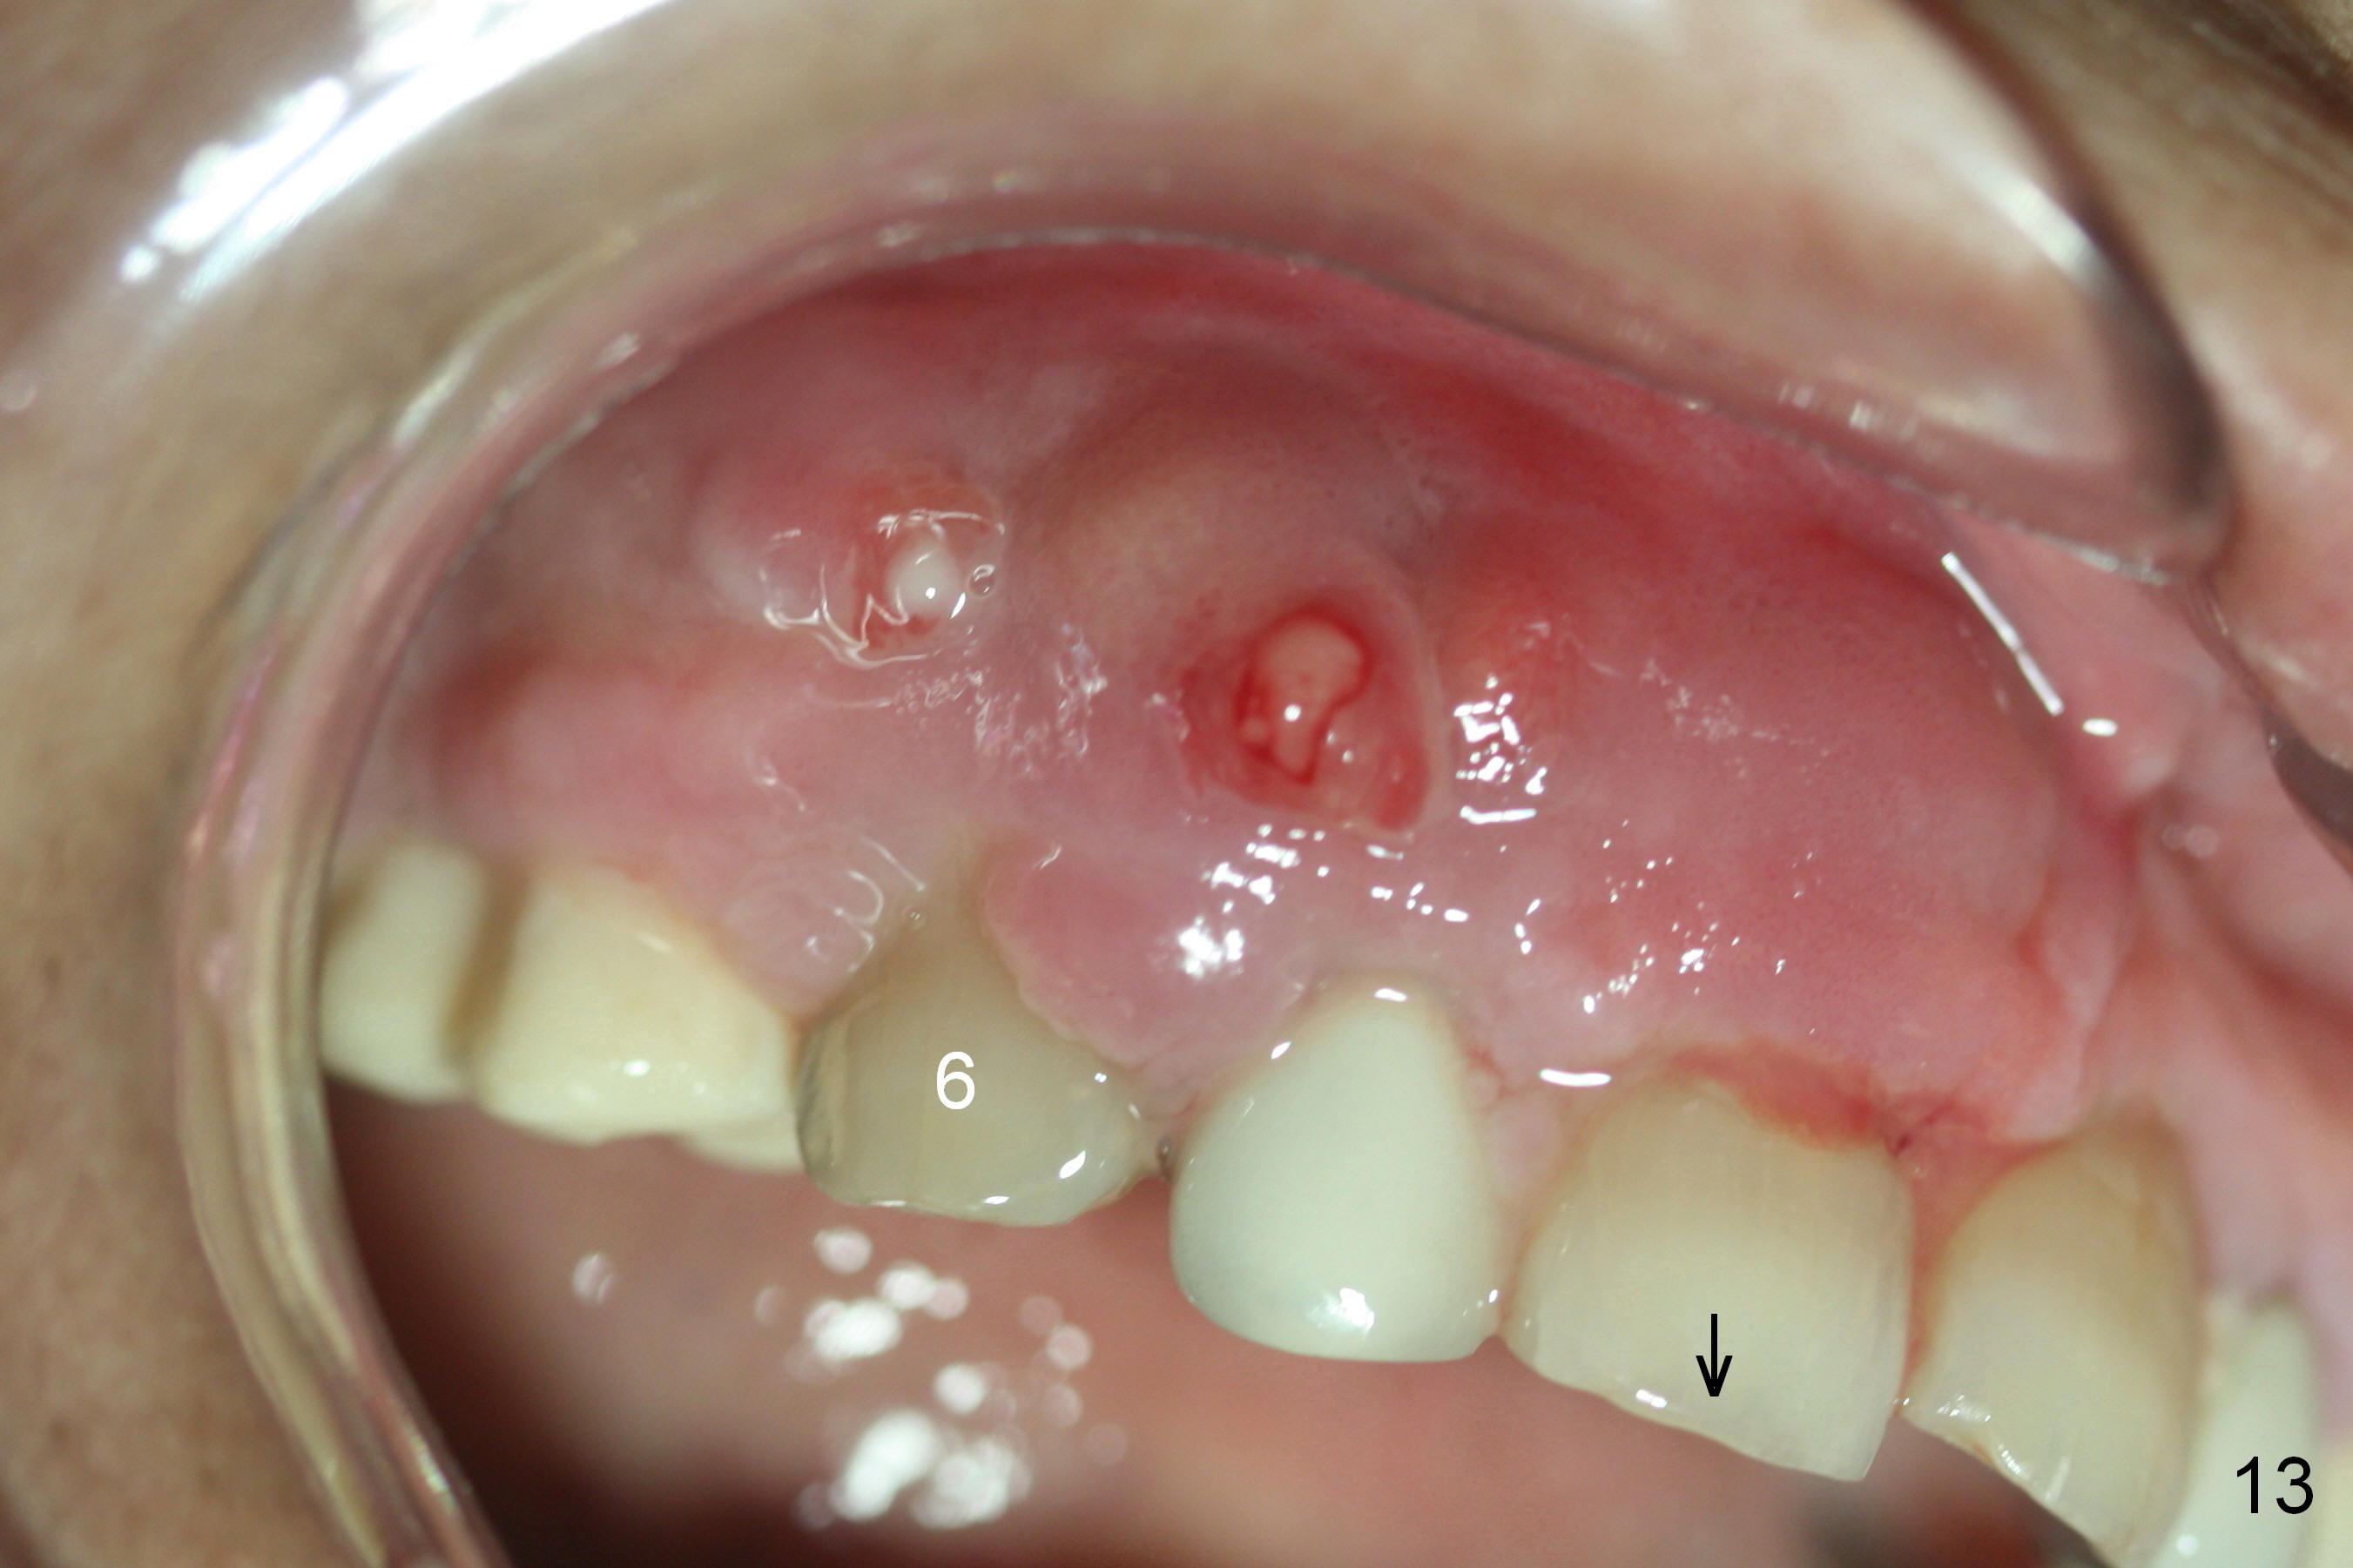

Preop photos show generalized gingival hyperplasia (hypertension med (Amlodipine, Calcium Channel Blocker), Fig.1 *), palatal (Fig.2<) and buccal (Fig.3 B) abscesses originated from the tooth #5. There is a smaller abscess buccal to the tooth #3 (not shown). After extraction, the buccal and palatal plates of the teeth #3 and 5 are found basically non-existent. When taps are placed, large socket defects are evident (Fig.4 *). In addition to sinus lift at #3 (Fig.5 black *), mineralized cancellous and cortical allograft (.5-1 and 1-2 mm) is placed around the implants with healing screws in place (white *). After the healing screws are removed and cemented abutments are placed, more allograft is packed (Fig.6-8 *). Closing the "dead" space in step may prevent immediately postop infection and peri-implantitis.

Although the patient feels better after taking Amoxicillin, the infection remains at #6-8 five weeks postop (Fig.12,13). The tooth #8 appears to be extruded with >10 mm buccal pocket. Water pik is recommended. It seems that the teeth #6-8 should be extracted and replaced with implants. Scaling & root planing should be tried first (Fig.11,12).